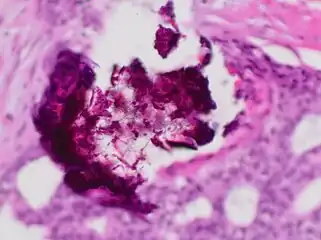

Mammogram microcalcifications in ductal carcinoma in situ Histopathology of dystrophic microcalcifications in DCIS, H&E stain.

Histopathology of dystrophic microcalcifications in DCIS, H&E stain. Histopathologic architectural patterns of DCIS.[24]

Immunohistochemistry for calponin in ductal carcinoma in situ, highlighting myoepithelial cells around all tumor cells, thereby ruling out invasive ductal carcinoma. Ductal carcinoma in situ with comedo necrosis spanning 30% of its diameter, which is generally regarded as the minimal size to classify it as comedo.[27]

Ductal carcinoma in situ with comedo necrosis spanning 30% of its diameter, which is generally regarded as the minimal size to classify it as comedo.[27]